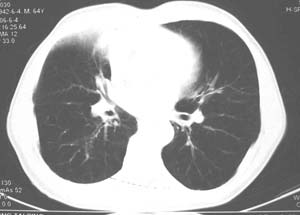

影像表现:肺窗示右肺上中叶均可见小片、条索状、小结状密度增高影,可见支气管充气相,小叶间隔增厚,支气管通畅,余肺未见明显异常。纵隔窗示4r可见小淋巴结融合,无明显肿大,右侧示少量胸腔积液。

影像学表现:右肺上叶大片状、网格状及索条致密影,前半部密实向后逐渐疏松,其内参杂斑点状小结节,密度不均匀,内见含气支气管像,纵隔内见肿大淋巴结.

右肺上叶见片状,网格状及索条样致密影,内见支气管气相,纵隔内见肿大淋巴结,同侧胸腔内少量液性密度影,余肺呈肺气肿改变,临床:男,64岁,咳血,咳痰,发热3天,wbc---1.2万